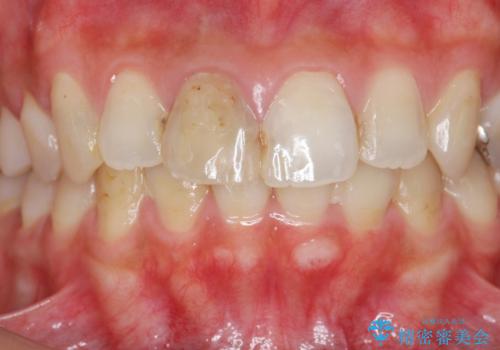

目立つ上顎前歯に変色・大きな虫歯治療痕が見られ、審美障害を引き起こしています。

虫歯の徹底的な除去、根管治療を行いセラミック治療に入る前の環境をしっかりと整えたのち審美的なジルコニアセラミックで治療を仕上げました。